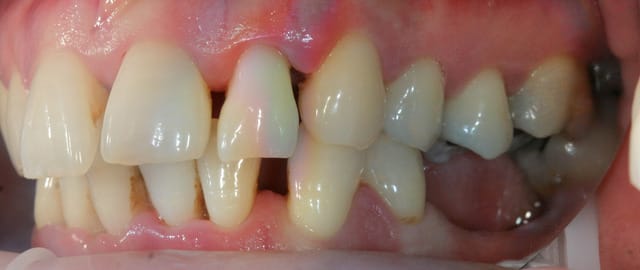

Paro ultra agressive chez une jeune femme de 30 ans.

Dans toute cette période, je n'ai pour ainsi dire quasiment jamais eu de cas de parodontite agressive aussi importante que celle ci.

Je me pose des questions non pas sur le traitement mais sur vos avis quant à la prédictibilité du traitement.

la patiente est très jolie, elle a 30 ans, a consulté deux ou trois dentiste en l'espace de 10 ans, le dernier détartrage date il y a trois ans et il n'a pas été terminée apparemment car la patiente avait trop de douleurs, et aujourd'hui elle est adressée par un hôpital parisien qui devait lui poser des implants et qui devant la panoramique a renoncé sans pour autant la diriger correctement.

Une contention sera réalisée en bas (mobilités très importantes) . En haut curieusement il n'y a que très peu de mobilités.

PS : ce qui me donne pas mal d'espoir dans ce cas-là, c'est tout de même les nombreuses lésions angulaires, qui vont bien accepter la pose de biomatériaux.